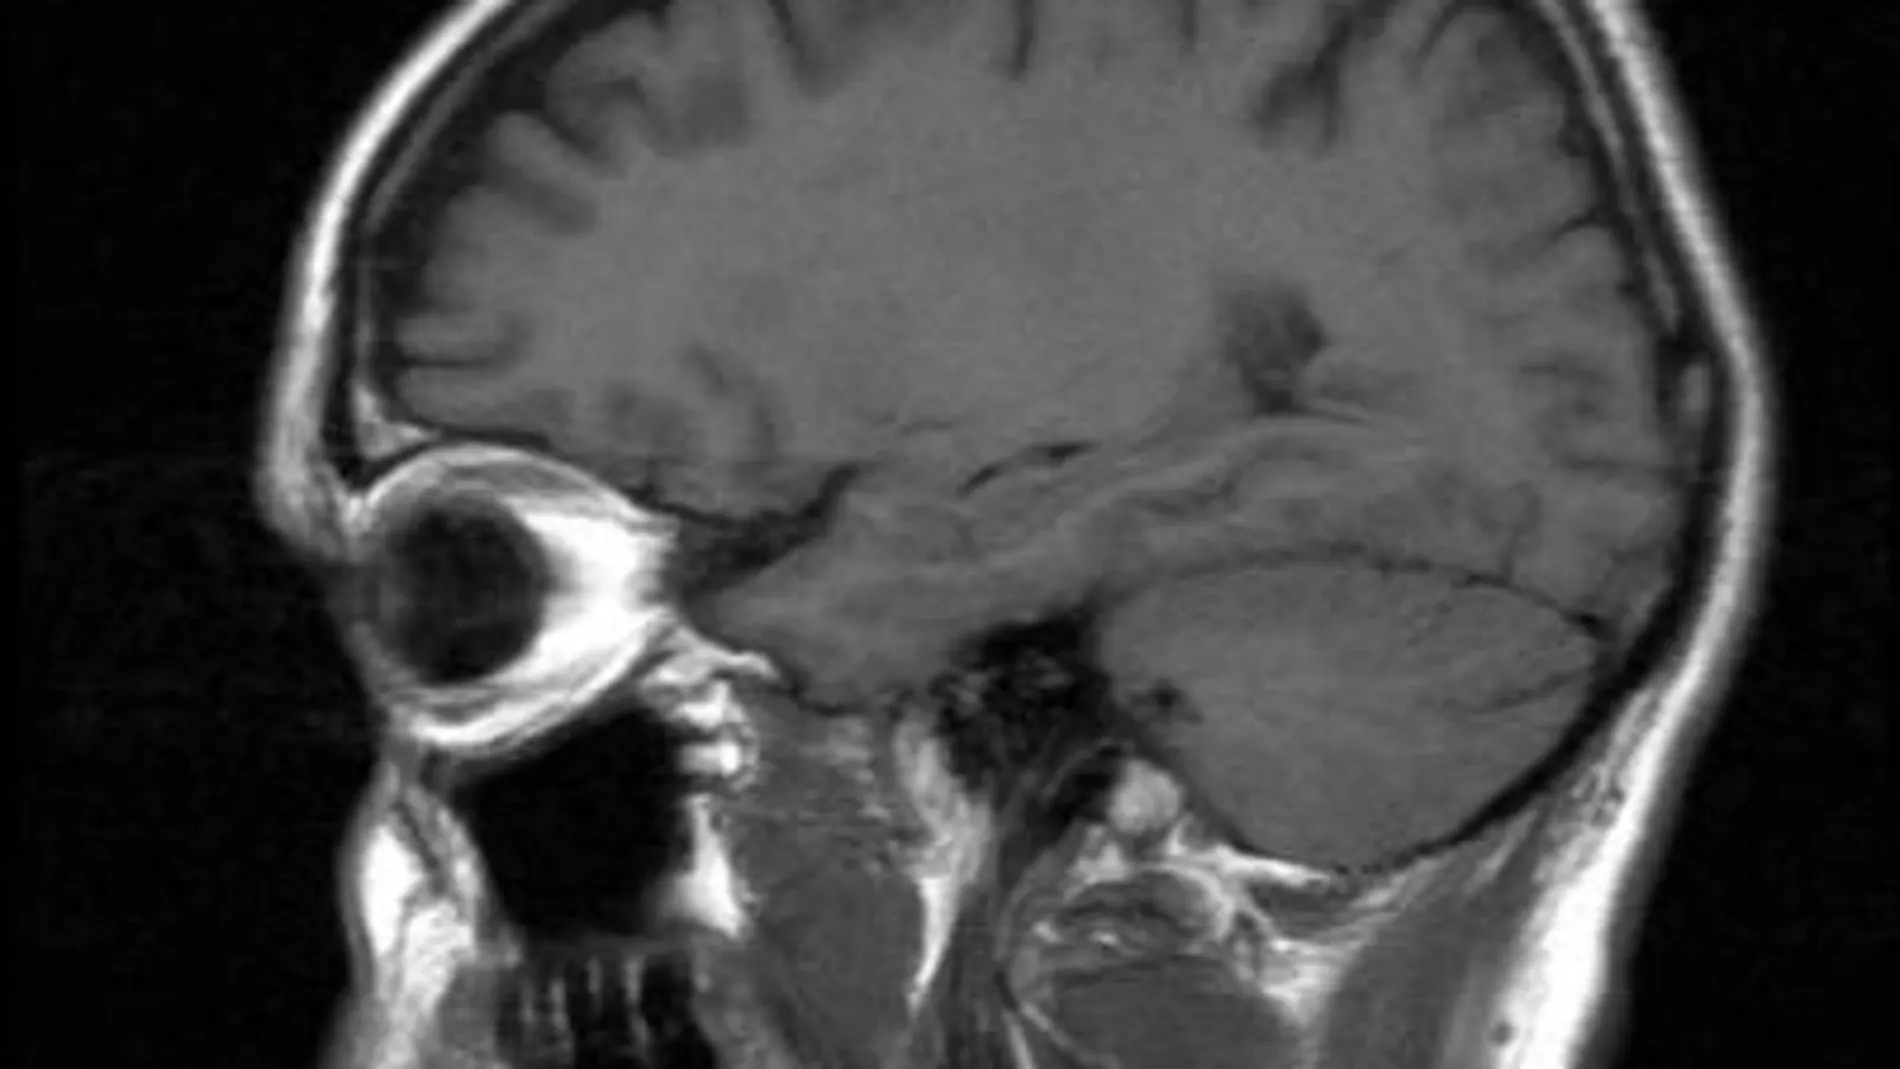

Los tumores cerebrales son una de las principales causas de mortalidad por cáncer en el mundo. Aunque en los últimos años se han conseguido importantes avances en el abordaje de los tipos más letales- debido, fundamentalmente, al desarrollo de la medicina molecular y de precisión- la barrera que "protege" el cerebro- denominada hematoencefálica- sigue siendo una frontera difícil de franquear, lo que dificulta en gran medida la eficacia de los tratamientos.

En los casos en lo que es posible, la mejor alternativa para los afectados suele ser la cirugía y la radiación, pero la extirpación incompleta del tumor y la toxicidad de la radiación pueden dejarles con problemas de salud de por vida tras el tratamiento, como disfunción neuroendocrina o pérdida de visión o memoria.

La segunda mejor opción es que funcionen medicamentos oncológicos ya existentes, ya que se conoce su efectividad y efectos secundarios a largo plazo. Esto es lo que ha descubierto un equipo de investigadores del Mass General Cancer Center, miembro del sistema sanitario Mass General Brigham de Estados Unidos, que han desarrollado un tratamiento dirigido con un éxito "sin precedentes" para los craneofaringiomas papilares (CFP), un tipo raro de tumor cerebral que causa una morbi-mortalidad muy elevada , según publica el New England Journal of Medicine, e informa Ep.

El equipo dirigió el primer protocolo de tratamiento multicéntrico de este letal tumor con dos medicamentos oncológicos existentes- vemurafenib y cobimetinib, ambos inhibidores del gen BRAF/MEK- que previamente habían mostrado que pueden interferir directamente con los genes defectuosos de los CFP para detener su progresión y reducir drásticamente su tamaño.

Basándose en este avance, los investigadores trataron a 16 pacientes como parte de un ensayo clínico de fase II y descubrieron que los tumores se reducían una media del 91% .Casi todos (15) completaron al menos un ciclo de 28 días de tratamiento. Siete pacientes no recibieron ningún otro tratamiento tras interrumpir el tratamiento con vemurafenib/cobimetinib y seis no han mostrado indicios de progresión tumoral en una mediana de seguimiento de casi 2 años. Ninguno tumor progresó y ninguno de los pacientes ha fallecido.

"Todos los pacientes que completaron uno o más ciclos de terapia respondieron al tratamiento, lo que supone la tasa de respuesta más alta hasta la fecha de cualquier terapia médica para tumores cerebrales", señaló la primera autora Priscilla Brastianos, directora del Centro de Metástasis del Sistema Nervioso Central dentro del Mass General Cancer Center, informa Ep. "Estos resultados sin precedentes señalan un cambio de paradigma para el tratamiento de los tumores cerebrales, ya que demuestran que, con el objetivo correcto y los fármacos adecuados, la medicina de precisión puede tener un impacto dramático", añadió